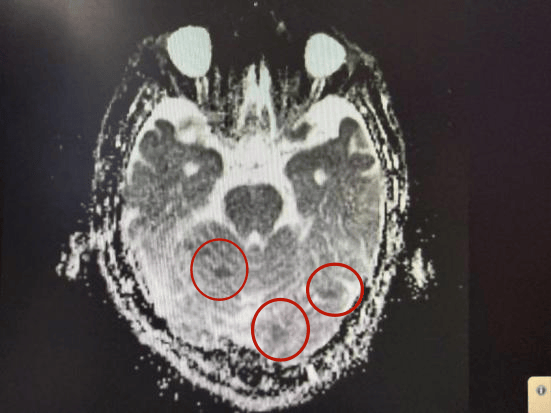

果不其然,复查的 DWI 影像清晰地显示出了多发性新发梗死灶!这一结果印证了宋梅最初的判断,也让患者和家属惊出一身冷汗。

“脑梗死在发病超早期可能存在 DWI 假阴性,这就需要我们临床医生练就‘火眼金睛’,不能只看报告不看病人,更不能被单一检查结果牵着鼻子走。”宋梅强调。